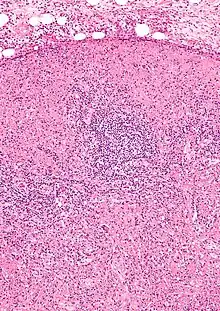

Micrograph of a lymph node with Kikuchi disease showing the characteristic features (abundant histiocytes, necrosis without neutrophils). H&E stain. | |